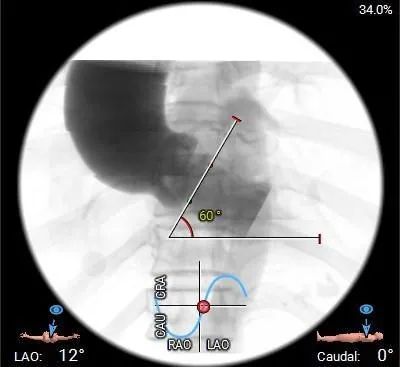

水平夹角测量:

虚拟瓣环与水平面夹角60°,横位心